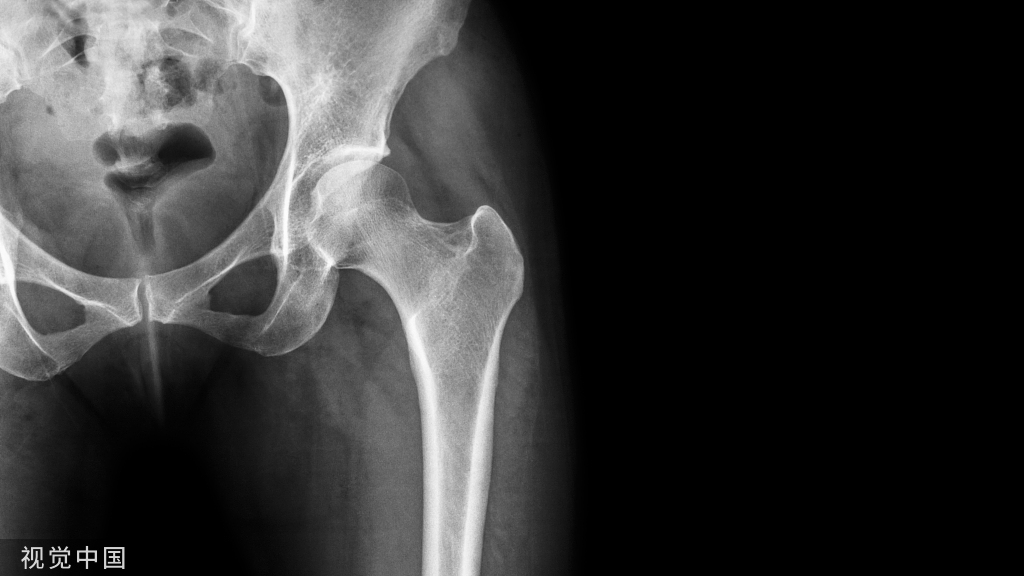

髋关节

(一)髋关节为多轴性关节,能作屈伸、收展、旋转及环转运动。但由于股骨头深嵌在髋臼中,髋臼又有关节盂缘加深,包绕股骨头近2/3,所以关节头与关节窝二者的面积差甚小,故运动范围较小。加之关节囊厚,限制关节运动幅度的韧带坚韧有力,因此,与肩关节相比,该关节的稳固性大。而灵活性则甚差。

(二)在髋臼的边缘有关节盂缘附着。加深了关节窝的深度。在髋臼切迹上横架有髋臼横韧带,并与切迹围成一孔,有神经、血管等通过。关节囊厚而坚韧,上端附于髋臼的周缘和髋臼横韧带,下端前面附于转子间线,后面附于转子间嵴的内侧(距转子间嵴约1厘米处),因此,股骨颈的后面有一部分处于关节囊外,而颈的前面则完全包在囊内。

(三)关节囊下部有耻骨囊韧带增强,可限制大腿过度外展及旋外。关节囊后部有坐骨囊韧带增强,有限制大腿旋内的作用。